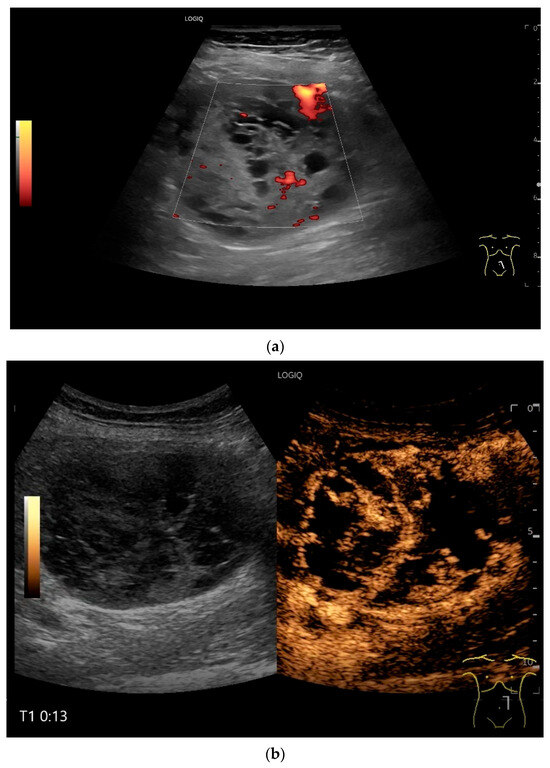

On US, small intestine NEN appear as small focal hypoechoic wall thickenings with a pseudo nodular appearance or as hypoechoic nodular lesion. They are usually small tumors. Adjacent pathological lymph nodes may appear in the mesentery. The tumors extend from the submucosa and may extend into the mesentery via the lamina muscularis propria [90,91,92,93,94,95,96]. NEN are usually well vascularized. Color Doppler imaging (CDI) can show irregular macrovessels in the tumor. Case reports showed that small intestine NETs are hyperenhanced on CEUS [91,92,94,95,96,97] (Figure 7 and Figure 8). Further diagnostics include CT and DOTATOC-PET.

Figure 7.

NET in the ileum. An oval polyp-like lesion is visible in the ileum (a). Small vessels are visible on power Doppler, indicating that the tissue is solid (b). In CEUS with 2.4 mL SonoVue (linear transducer 2–9 MHz), the tumor capsule shows enhancement. The tumor is marked with white arrows. At 22 s, vessels can be distinguished in the tumor, but there is no complete enhancement of the tumor. The ileum wall is also enhanced (yellow arrow) (c). Even at the end of the arterial phase at 34 s, the tumor is not completely enhanced. Two macro vessels are marked with an arrow. Distally, they show irregular vessel branches (d). The tumor was not located directly behind the ileocecal valve. Based on the US findings, the endoscope was inserted 20 cm into the terminal ileum, where the tumor was then discovered.

Figure 8.

NET in the ileum. In the terminal ileum, there is a slight wall thickening <5 mm (arrow), but with loss of stratification (a). The tumor (arrow) changes position with peristalsis while the transducer position remains the same. With the 9 MHz linear transducer, the five layers of the unremarkable wall and Kerckring folds (KF) are visible (b). Small vessels can be distinguished in power Doppler (c).

Figure 9.

Burkitt-Lymphoma. In a patient with weight loss, increased abdominal circumference, anemia, and physical weakness, the initial sonographic examination reveals an extensive tumor with intense hypoechogenicity and a connection to the jejunum in the left mid-abdomen. Despite its pronounced hypoechogenicity, a feeding vessel on CDI indicates a solid character (a). The tumor significantly thickens the wall and is intensely hypoechoic. The arrows point to the multisegmental hypoechoic wall thickenings (b). Normal wall structures are still visible (W), and the tumor extends beyond the wall (arrow) (c). In addition to delicate Kerckring folds (KF), there are significantly polypoid thickened KF with pronounced hypoechogenicity (d). The thickening of KF is very extensive (e). Wall thickening was found also in the stomach and colon and allowed endoscopic biopsy to establish the diagnosis.

Figure 10.

Diffuse large B-cell lymphoma (DLBCL). In the right mid-lower abdomen, a large, smoothly circumscribed mass is present around the ileum (“pseudo kidney sign” (a)). Using a high-resolution linear transducer, the mass appears smoothly circumscribed and almost anechoic (b). The ileum runs centrally, and the echogenic wall is clearly defined (c). This wall does not merge into the mass. Since the mass is almost anechoic, it is also difficult in different transducer positions to distinguish whether it is a liquid lesion or a solid mass (b,c). CEUS with 2.4 mL SonoVue (9 MHz linear transducer) shows homogeneous arterial enhancement (d), but the intensity decreases with time in the venous phase (e). The ileal wall enhancement centrally within the mass is more intense than that of the tumor (d,e).